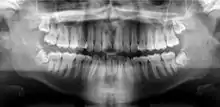

Галерея

На панорамной рентгенограмме зубов видна зубная киста (отмечена стрелкой).